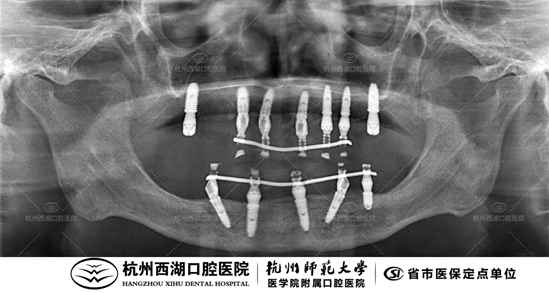

术后CBCT照如下